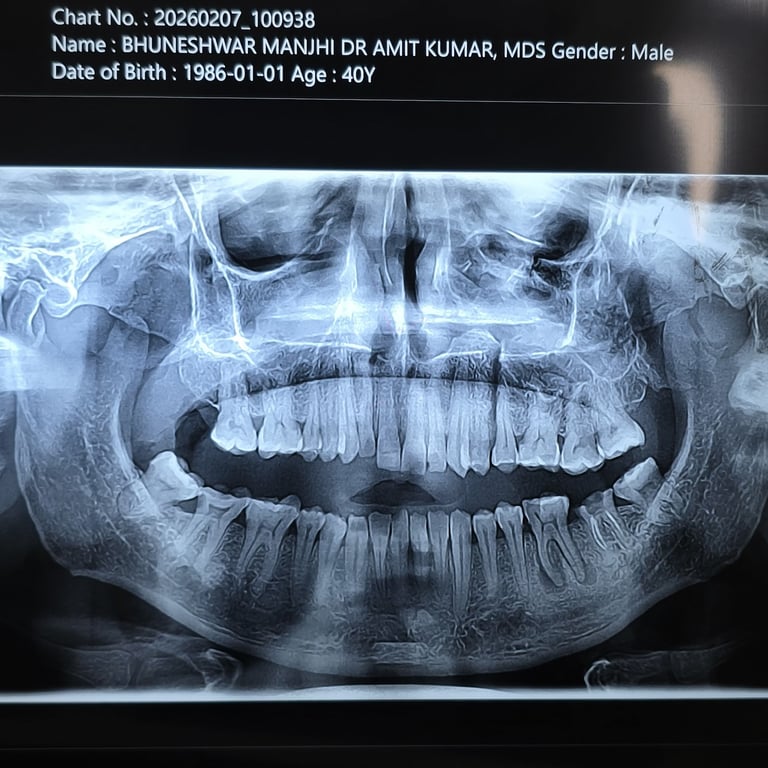

UPPER JAW FRACTURE